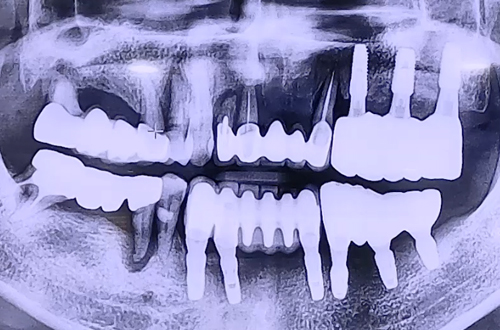

AFTER

환자분은 이전 왼쪽에 임플란트를 진행하셨었고,

임플란트가 되지 않은 오른쪽 위아래 어금니와 위 앞니가 심하게 흔들거려서

거의 왼쪽으로만 식사를 하고 계시는 상태에서 내원해 주셨습니다.

때문에 오른쪽 위아래 어금니와 윗니 앞니를 임플란트를 통해서 단단히 하고

치아의 기능을 회복시켜드리는 방향으로 치료 계획을 세웠는데요.

불편한 치아들을 발치하고 임플란트를 단단히 심어드렸고,

임플란트는 굉장히 단단하게 잇몸뼈와 잘 결합되고 주변 뼈이식까지 잘 진행되었어요.

만약 심으려는 임플란트가 단단할 경우 당일에 바로 임시치아를 체결해 드리는데

환자분게서는 위 앞니 주변 잇몸뼈들이 약해서 즉시 임시치아 체결은 불가능했습니다.

따라서 위 앞니 임플란트를 잇몸 속으로 완전히 묻어두고 시간이 지나 스스로 굳게 하기로 하고

임시치아는 끼우고 빼는 타입으로 제작하여 드렸던 케이스입니다.